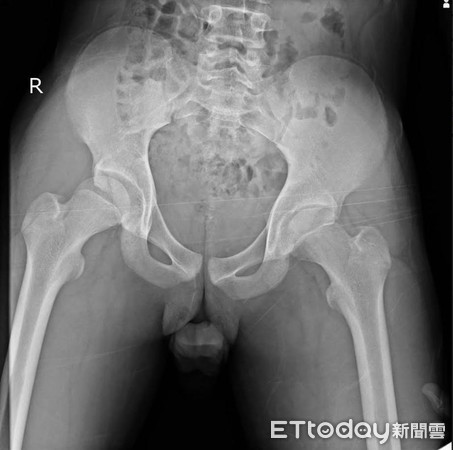

骨科王證琪醫師指出,這名患者來院時右腳呈現屈曲、內收及內轉姿勢,X光檢查發現其髖關節後側脫臼,於是安排開放性復位手術,發現髖臼關節唇(labrum)破裂並且卡在股骨頭與髖臼之間,在取出破裂的軟組織後,關節確實復位,術後也恢復良好。

▲髖關節脫臼可能會合併股骨頭骨折或髖臼骨折。

王證琪表示:「青少年的髖關節脫臼並不常見,通常是由高能量的創傷,例如車禍等意外所造成。」髖關節脫臼是骨科的急症,需要即時復位,同時也需留意是否有血管、神經、或是其它器官的損傷,髖關節脫臼有時會合併股骨頭骨折或髖臼骨折。脫臼的關節經由徒手復位之後有可能也會發生小碎骨卡入關節內,或是像這次的案例,是破裂的關節唇卡入關節內,這些狀況都必須仔細診察並即時處理。